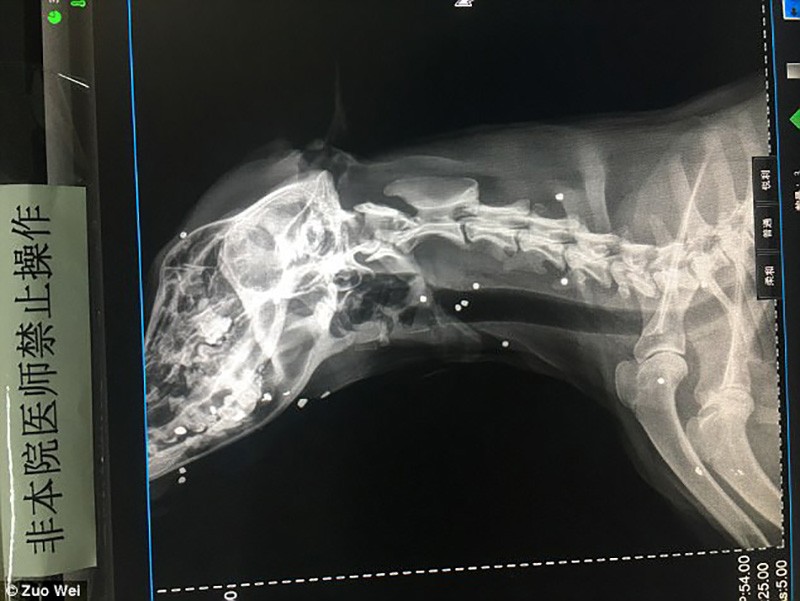

A férfi azonnal állatorvoshoz vitte barátját, ahol megállapították, hogy legalább 50-szer lőttek bele légpuskával a kutyába, ami gazdája szerint egyértelműen állatkínzás.

Szavait a röntgenfelvételek is alátámasztják, melyeken többek között az is látszik, hogy lövedék fúródott Er Mao agyába és az egyik szemébe is.

A kutya majdnem két hónap alatt, három sebészeti műtéten esett át, mire kiengedhették a kórházból. Megpróbáltak annyi lövedéket eltávolítani a testéből amennyit csak lehetett, de így is maradt 9, amit túl kockázatos lett volna kivenni, beleértve azt a golyót is ami a szemén keresztül fúródott az agyába.